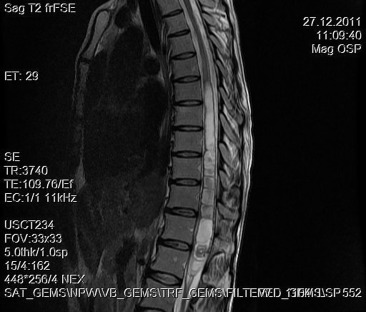

A 30-year-old woman was admitted to our clinic with complaints of back pain, walking disturbance, and progressive numbness in both legs for 2 months. Neurological examination was normal except for mild paraparesis in both legs. She had no bladder or bowel involvement. Magnetic resonance imaging (MRI) disclosed an 18 mm × 13 mm intramedullary tumor at the level of T12–L1 vertebrae. The tumor was hypointense on T1-weighted images (Fig. 1) and hyperintense on T2-weighted images (Fig. 2). Marked homogeneous contrast enhancement was noted (Fig. 3). There was associated syringomyelia extending from T7 down to the level of T12. The patient underwent T12 total laminectomy, and after exposition of the tumor, a biopsy was taken for frozen section analysis. Frozen section results were consistent with schwannoma. The tumor was heavily bleeding and highly adherent to the neural tissue of the spinal cord. Intramedullary tumor was removed subtotally using microsurgical techniques. Neurological examination improved postoperatively. Pathological examination revealed schwannoma (Fig. 4A and B).

Sagittal T2-weighted magnetic resonance imaging between T12 and L1 demonstrates ...

Figure 2.

Sagittal T2-weighted magnetic resonance imaging between T12 and L1 demonstrates a hyperintense tumor. Syrinx formation is seen.